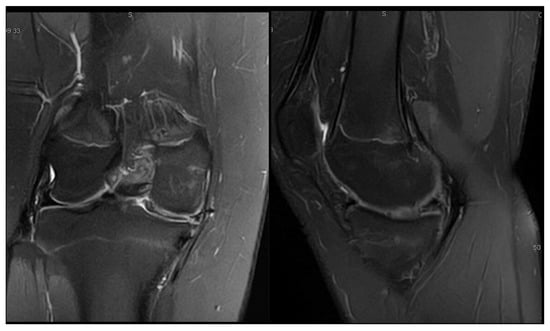

3.2. Case 2—S.C.S.

| S.C.S. | 13 | Left | Pain, occasional locking, normal ROM | Dancing | 1 surgery: partial meniscectomy and suture for horizontal tear (13) | 6 months: symptom-free, full ROM, resumed dancing |